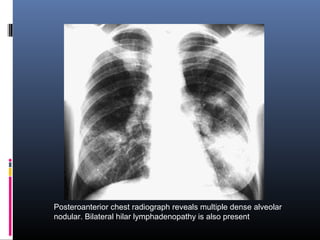

Posteroanterior chest radiograph reveals multiple dense alveolar

nodular. Bilateral hilar lymphadenopathy is also present

Posteroanterior chest radiographreveals multiple dense alveolar nodular. Bilateral hilar lymphadenopathy is also present

• #27 (A) Nodular sarcoidosis. Posteroanterior chest radiograph reveals multiple dense alveolar nodular infiltrates in a 36-year-old woman. Bilateral hilar lymphadenopathy is also present. Transbronchial lung biopsies demonstrated confluent noncaseating granulomas consistent with sarcoidosis. The infiltrates resolved following institution of corticosteroid therapy.